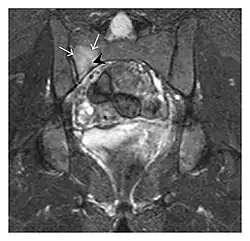

The sacrum is usually masked by overlapping bowel gas in conventional radiographs, and the subtle radiographic findings are usually nondiagnostic and even misleading. The characteristic "H" pattern has been correlated with biomechanical models of patient activities. The vertical parasagittal planes correspond to the region of maximal stress during walking, while the horizontal fracture develops later, secondary to the loss of lateral support by parasagittal fractures. MRI is the primary imaging technique in this case, with the most common MRI pattern showing bone marrow edema and a fracture line (Figure 12). Coronal views are quite contributive in sacral fractures, allowing the detection of the horizontal component, especially with fluid-sensitive sequences. Although the sacrum is the most commonly involved, pelvic insufficiency fractures are often multiple, and other typical locations should be mentioned.[1]

Proximal femoral fractures usually occur in osteoporotic patients, and their signs include subtle neck angulation, trabecular angulation, and subcapital impaction line. A frog-leg lateral view may be helpful if the greater trochanter is short enough. However, positioning can be difficult because of hip pain. In patients with strong suspicion of proximal femoral fracture and negative radiographs, MRI limited to coronal T1 W images and scintigraphy can be highly valuable (Figures 13 and 14). Such an option, with limited examination time, is cost-effective and allows reliable exclusion or confirmation of the diagnosis, preventing an unnecessary stay at the hospital or delayed treatment. Moreover, MRI helps to detect soft tissue abnormalities which are more frequently seen in femoral, acetabular, and pubic injuries than sacral lesions. Concomitant fractures are also frequently seen in typical pelvic sites.[1]

a

b

Figure 13: Partial osseous avulsion of the gluteal muscles at the greater trochanter in a 59-year-old man who presented with the right hip pain without a history of trauma. Lauenstein view and anteroposterior and radiographs (not shown) did not show an obvious fracture line or disruption of bony contours in the acetabulum or the right femoral neck. (a) Coronal T1-weighted MRI displays an incomplete fracture line extending partially from the greater trochanter (arrow). (b) Coronal short tau inversion recovery MRI shows heterogeneous hyperintensity in the same region (arrow) as well as hyperintensity within the gluteus medius and minimus muscles (arrowheads) consistent with tissue edema and hematoma.[1]

Figure 14: Subcapital insufficiency fracture in a 55-year-old man with a left hip pain without a history of trauma. Anteroposterior and Lauenstein view radiographs centered on the left hip do not show an obvious fracture line, but mild acetabular osteophytosis was noted consistent with hip osteoarthritis (not shown). (a) Coronal T1-weighted MRI shows a linear low-signal band through the femoral neck corresponding to a fracture line (arrowheads). (b) Bone scintigraphy shows focal uptake (arrow) corresponding to the fracture.[1]